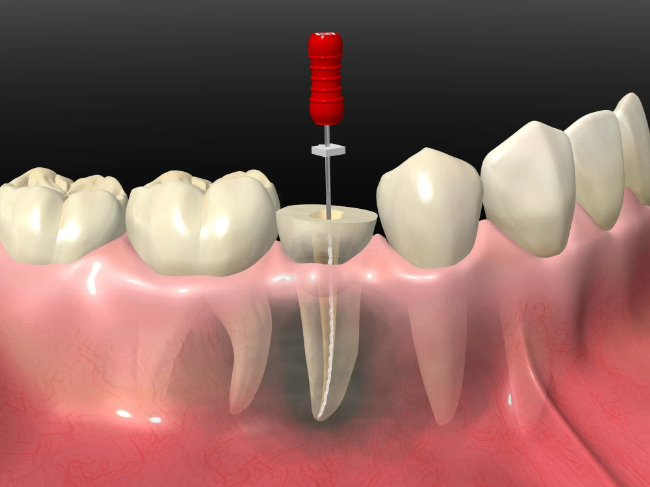

根管治療とは、虫歯などで歯の神経が炎症を起こした際に、根管内の神経や汚染物を取り除く治療のことです。虫歯の初期段階では、違和感や痛みが出ることはほとんどありません。

しかし、歯の内部まで虫歯が進行すると、神経が炎症を起こし、激しい痛みが出ることがあります。根管治療では、歯の内部にある神経や血管を除去し、根管内を洗浄・消毒します。その後、薬剤を詰め、土台を立ててから被せ物を装着して歯の機能を回復させます。

抜髄(ばつずい)

炎症を起こした歯の神経を取り除くことを、抜髄といいます。ファイルやリーマーという器具を使用して根管内の神経や血管を取り除きます。

根管内は非常に細く、枝分かれしていることが多いです。また、無理な力で器具を動かすと、根管に穴が空いてしまうこともあります。そのため、慎重に器具を動かしながら、治療が進められます。

根管充填

根管内の洗浄と消毒ができたら、最終的な薬剤を詰めます。薬剤を根の先までしっかり充填することで、虫歯の再発を予防する効果があります。